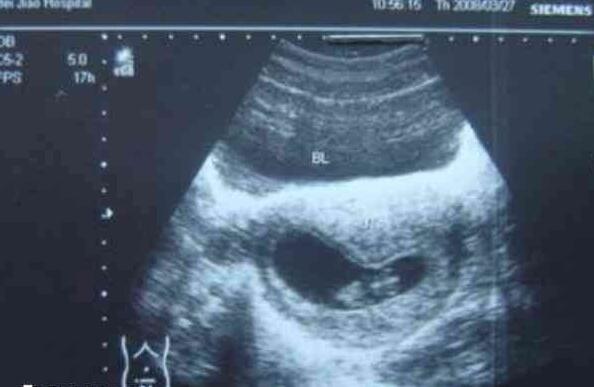

2、怀孕6周:停经6周左右进行彩超检查,排除宫外孕,如果孕前未进行优生筛查,可以完善检查;

3、怀孕7周:停经7周左右做超声检查,确定是否有胎心、胎芽的出现以及发育情况,还要抽血检查甲状腺功能;